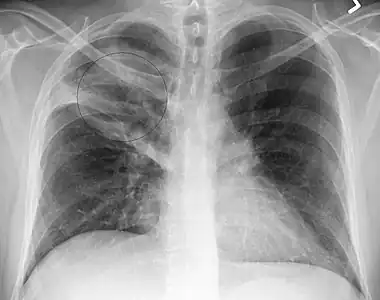

Right upper lobe pneumonia as marked by the circle. -